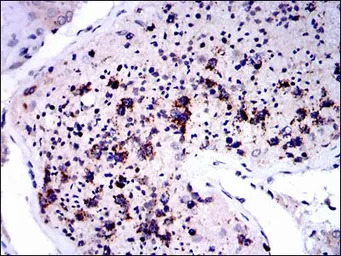

IHC-P analysis of human testis tissue using GTX60523 NQO1 antibody [4D12].

IHC-P analysis of ovarian cancer tissue using GTX60523 NQO1 antibody [4D12].